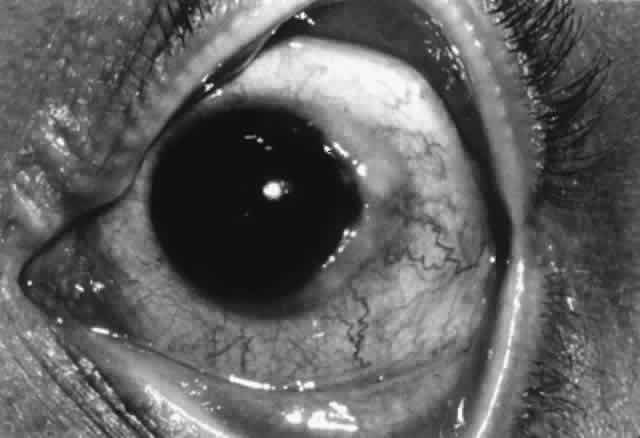

Type I: Immediate Hypersensitivity (Anaphylaxis) Type I hypersensitivity involves antigen binding to IgE bound to the surface of mast cells and subsequent cross-linking. This stimulates mast cell degranulation and release of preformed mediators (e.g., histamine). In addition, there is de novo synthesis of inflammatory mediators such as prostaglandins, leukotrienes, and PAF. The result is smooth muscle contraction, increased vascular permeability, and vasodilation. This is the predominant mechanism of allergic reactions and is discussed more fully elsewhere (see Mast Cells, and Allergic Conjunctivitis). Type II: Antibody-Dependent Cytotoxicity In type II reactions, complement-fixing antibody (e.g., IgM, IgG1, IgG2, IgG3) binds to the target cell. Complement then binds to this antibody, activating the classic pathway. The result is cell lysis. This is the pathogenic mechanism seen in Goodpasture's syndrome and in hemolysis in transfusion reactions. Pemphigoid, pemphigus, Mooren's ulcer, and thyroid-related orbitopathy are considered examples. Antibody-dependent cell-mediated cytotoxicity (i.e., K-cell activity) has also been categorized under type II reactions, although there is an obvious overlap with cell-mediated immunity. Type III: Immune Complex-Mediated Hypersensitivity (Arthus Reaction) Low levels of immune complexes are found in normal individuals as a result of antibody binding to antigen; these complexes are cleared by cells of the reticuloendothelial system. This process represents an effective mechanism of normal host defense. However, depending on certain factors (e.g., size of the immune complex, immunoglobulin class, antigen characteristics, hemodynamic turbulence), immune complexes can be deposited in tissues such as vascular walls and renal glomeruli. If these complexes contain IgM or IgG1–3, the complement cascade can be activated with release of chemotactic factors, neutrophil accumulation, and subsequent degranulation and enzyme release, causing local tissue damage. This mechanism is responsible for vasculitis and glomerulonephritis. Corneal immune ring formation is the result of immune complex deposition. Immune complex deposition was classically considered a major player in noninfectious uveitis; however, now its role is less clear. For example, Behçet's disease was thought to be the prototype of immune complex-mediated disease, yet T-cell-mediated mechanisms are also involved.12 Type IV: Cell-Mediated Hypersensitivity (Delayed Hypersensitivity) Type IV hypersensitivity was initially termed delayed hypersensitivity to describe those reactions that took more than 12 hours to develop. These reactions were found to be transferable to nonimmunized hosts by lymphoid cells but not serum, indicating the cell-mediated nature of this type of immune response. Classically, four types of type IV delayed hypersensitivity reactions have been described, based on characteristic skin reactions to antigen. These types include the Jones-Mote reaction, contact hypersensitivity, tuberculin-type hypersensitivity, and granulomatous inflammation. However, in practical terms, there is considerable overlap. To generalize, type IV cell-mediated hypersensitivity occurs as a result of class II-restricted antigen presentation by Langerhans cells or macrophages and IL-1 production, leading to helper T-cell stimulation and lymphokine release. This triggers a complex cellular response including recruitment of B cells, cytotoxic T cells, macrophages, and, to a lesser extent, neutrophils. Mechanisms of damage include cell-mediated cytotoxicity, phagocytosis, enzymatic processes, and, in the case of persistent antigen, epithelioid and giant cell formation (i.e., granulomatous inflammation). Type IV reaction plays a major role in virus infection, tuberculosis, leprosy, and fungal infection. Sympathetic ophthalmia and Vogt-KoyanagiHarada syndrome, corneal graft rejection, phlyctenulosis, and contact allergy are all type IV reactions. The Jones-Mote reaction is also known as cutaneous basophil hypersensitivity. It has been described as a unique form of type IV hypersensitivity in which there is a predominance of basophils. This form of hypersensitivity peaks at 24 hours, as opposed to contact and tuberculin reactions, which peak at 48 to 72 hours, and granulomatous reactions, which take 3 to 4 weeks to develop. It plays a role in vernal keratoconjunctivitis and contact lens-related giant papillary conjunctivitis (GPC). Type V: Stimulating Antibody Type V hypersensitivity is an antibody-mediated reaction in which autoantibody binds to cell receptors normally occupied by another molecule. This may lead to stimulation of the target cell (e.g., Graves' disease). AUTOIMMUNITY Tolerance Through its inherent specificity and through certain protective mechanisms, the immune system is able to differentiate self from nonself. Tolerance to self may be attained by removal of autoreactive T-cell clones during development (clonal deletion). Another possible mechanism is clonal anergy by which B cells are rendered unresponsive to self-antigen by exposure at an early stage of development. Other possible mechanisms include sequestration of autoantigen, absence of processing and presentation of self-antigen, receptor blockade by antigen, anti-idiotype antibodies, and activity of suppressor T cells that down-regulate potential autoreactivity.13,14 However, the safeguards of immunologic self-tolerance can malfunction, resulting in immune reactions against self (i.e., autoimmunity). Several mechanisms have been implicated. Mechanisms of Autoimmune Disease In normal persons, autoreactive B cells and T-effector cells and autoantigens are present; however, these are not normally active because autoreactive helper T cells are functionally absent.13 Under certain circumstances, functional autoreactive helper T cells may emerge either by dysfunction of suppressor cells or by the action of T-contrasuppressor cells (which enable anti-self helper T cells to resist suppression). Also, it is possible that in some cases autoantigen may bypass helper T cells altogether and directly stimulate T-effector cells and B cells. Also, suppressor T cells that normally prevent antibody production to self-antigen could become inactivated. Another possible autoimmune mechanism involves inappropriate expression of class II molecules on cells that normally do not possess this cell marker. This can occur in some diseases, especially in the presence of IFN-γ. This conveys to these cells the ability to act as antigen-presenting cells promoting inappropriate presentation of self-antigen. This may result in activation of helper T cells, leading to B-cell production of autoantibodies and/or activation of cytotoxic T cells. Cross-reactivity may play a role. Alteration of self-antigen (e.g., by drugs or viruses) may enable helper T cells to function as self-reactive T-helpers and thus to generate an autoimmune response. Alternatively, the normal T- and B-cell response to foreign antigen that possesses a structure resembling self-antigen may produce antibodies that cross-react with those self-antigens of similar structure. This is known as molecular mimicry. Nonspecific activation of the immune system by polyclonal activators (e.g., Epstein-Barr virus or bacterial lipopolysaccharides) may overwhelm normal immunoregulatory mechanisms and promote autoimmune disease. Anti-idiotype antibodies may normally play a role in controlling the immune response by binding the idiotype portion of surface immunoglobulin on B cells and suppressing B-cell antibody production. Dysfunction of anti-idiotype antibodies could lead to B-cell hyperactivity and could play a role in autoimmune disease. Some autoantibodies play a role in autoimmune disease by their effect on surface receptors. Autoantibodies can bind to cell-surface receptors and act as agonists. An example is Graves' disease, in which an autoantibody (long-acting thyroid stimulator [LATS]) binds to the thyroid-stimulating hormone (TSH) receptor, delivering the same stimulus as TSH and driving thyroid hormone production. Other autoantibodies can block cell-surface receptors, preventing binding of hormones or other molecules to their appropriate receptors and resulting in dysfunction. An example is myasthenia gravis, in which autoantibodies bind to acetylcholine receptors on the motor endplate, resulting in defective neuromuscular transmission. Genetic factors play a role in autoimmunity, as there are HLA associations with certain autoimmune diseases (e.g., Graves' disease and HLA-B8, -DRw3 in whites; ankylosing spondylitis and HLA-B27). Tissue injury in autoimmune disease may occur by a number of mechanisms. Type II reactions can be involved. Circulating autoantibodies may react with self-antigens on the cell surface, triggering complement activation and cell lysis via the membrane attack complex. Also, autoantibody binding can lead to activation of cytotoxic cells, resulting in cell lysis. A second mechanism involves type III reactions. Autoantibodies may bind to free antigen, forming circulating immune complexes that deposit in tissue, followed by complement activation and subsequent inflammation. Type IV (cell-mediated) hypersensitivity mechanisms also play a role in autoreactivity. IMMUNOSUPPRESSIVE AGENTS A classification of immunosuppressive agents is presented in Table 3. The mechanism of action of selected agents more commonly used in the treatment of ocular inflammatory disease is discussed.